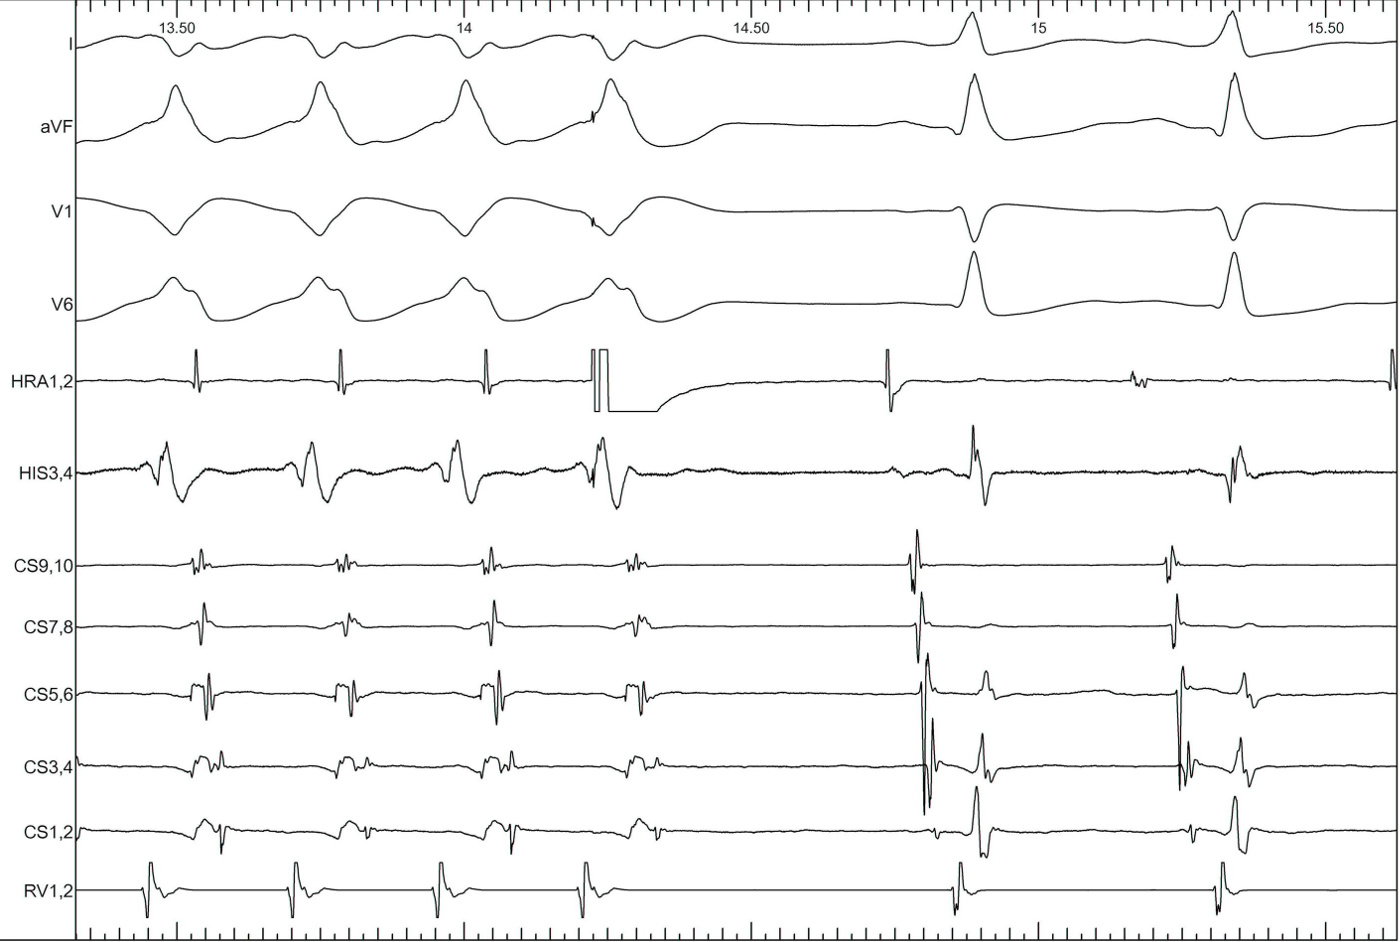

Example

entrainment_egm.jpg